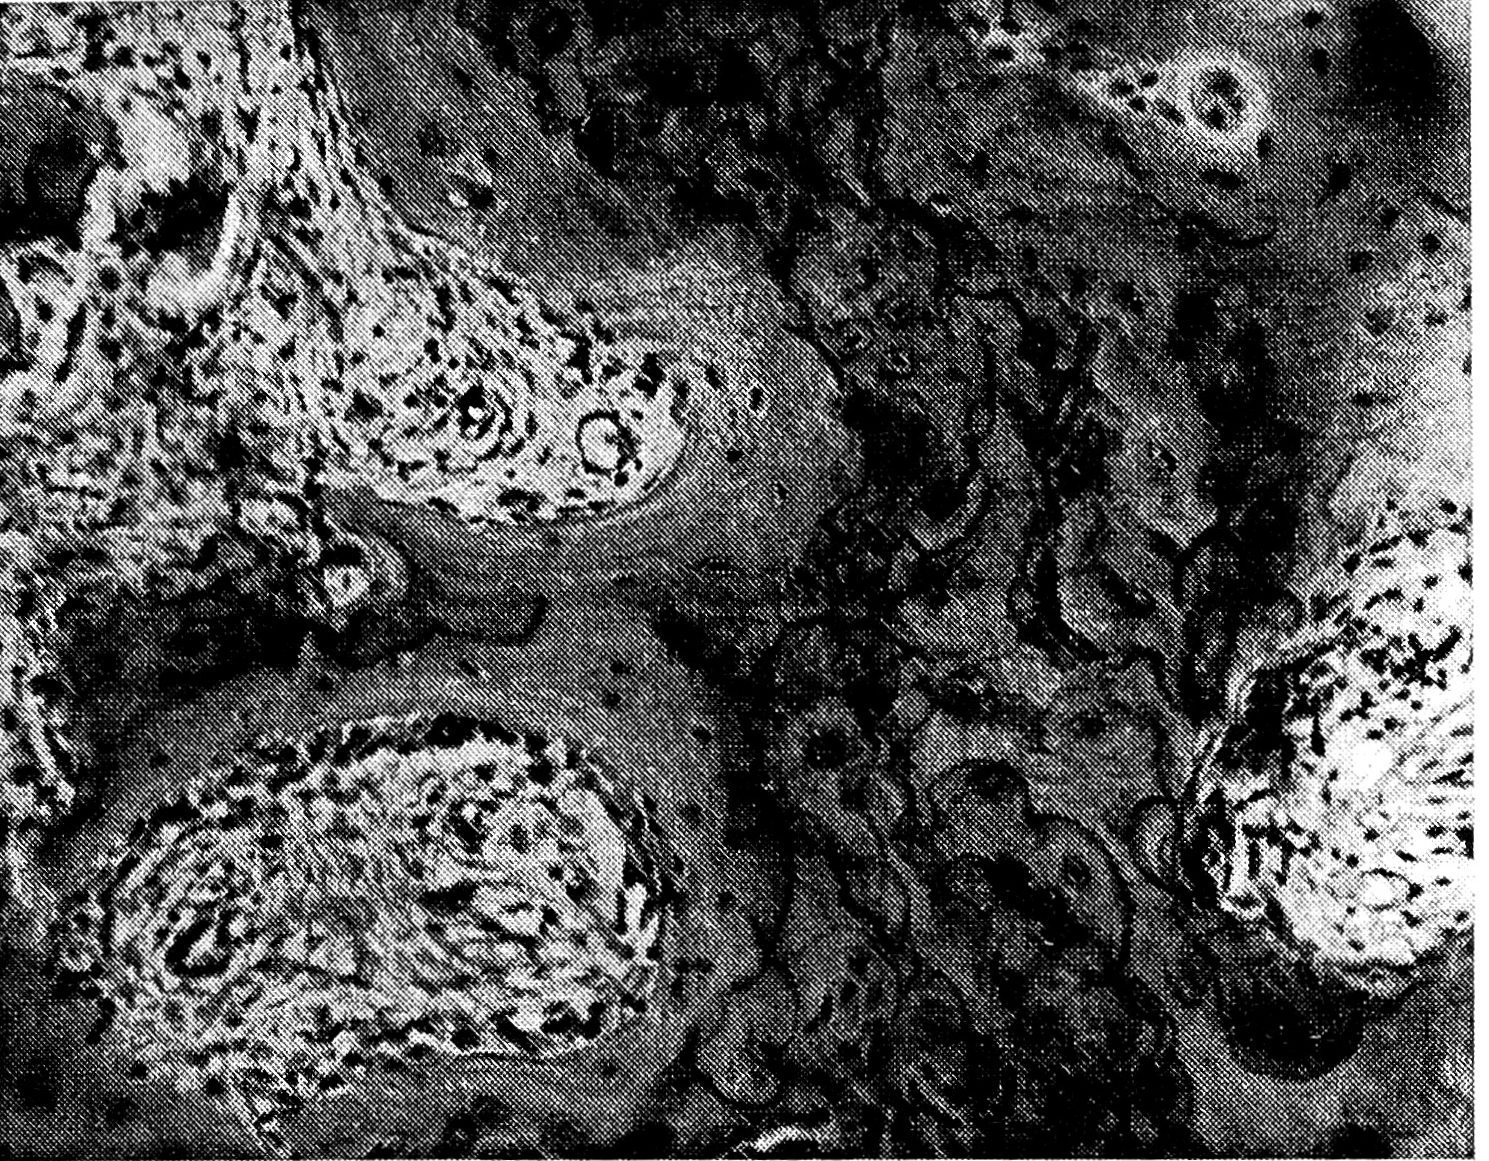

I стадия — стадия остеолиза — характеризуется преобладанием процессов выраженного разрушения костной ткани (рис. 1). При этом наблюдается значительное увеличение числа остеокластов, принимающих активное участие в резорбции минерализованной кости. Лизис кортикальной костной ткани в основном происходит со стороны эндоста, но может наблюдаться также и со стороны периоста. Отмечается постепенное расширение гаверсовых каналов, в просвете которых определяется разрастание клеточно-волокнистой соединительной ткани, богатой функционально активными клеточными элементами. В этой ткани, кроме остеокластов, в основном контактирующих с костной тканью, определяются гистиоциты, остеобластоподобные и фибробластоподобные клеточные элементы. Обычно в ней наблюдается большое число расширенных и полнокровных кровеносных сосудов. Следует сказать, что в стадии остеолиза отмечается и расширение фолькмановских каналов кортикальной кости, которые также заполнены разрастающейся клеточноволокнистой тканью. Постепенное расширение гаверсовых и фолькмановских каналов за счет резорбции их стенок приводит к рарефикации (спонгизации) компактной кости.

Рис. 1. Резорбция кортикальной кости со стороны расширенных фолькмановских и гаверсовых каналов, в которых определяется клеточно-волокнистая ткань, содержащая многочисленные остеокласты. I стадия заболевания.

Кристеллеровский срез, окраска гематоксилином и эозином. Ув. 80.